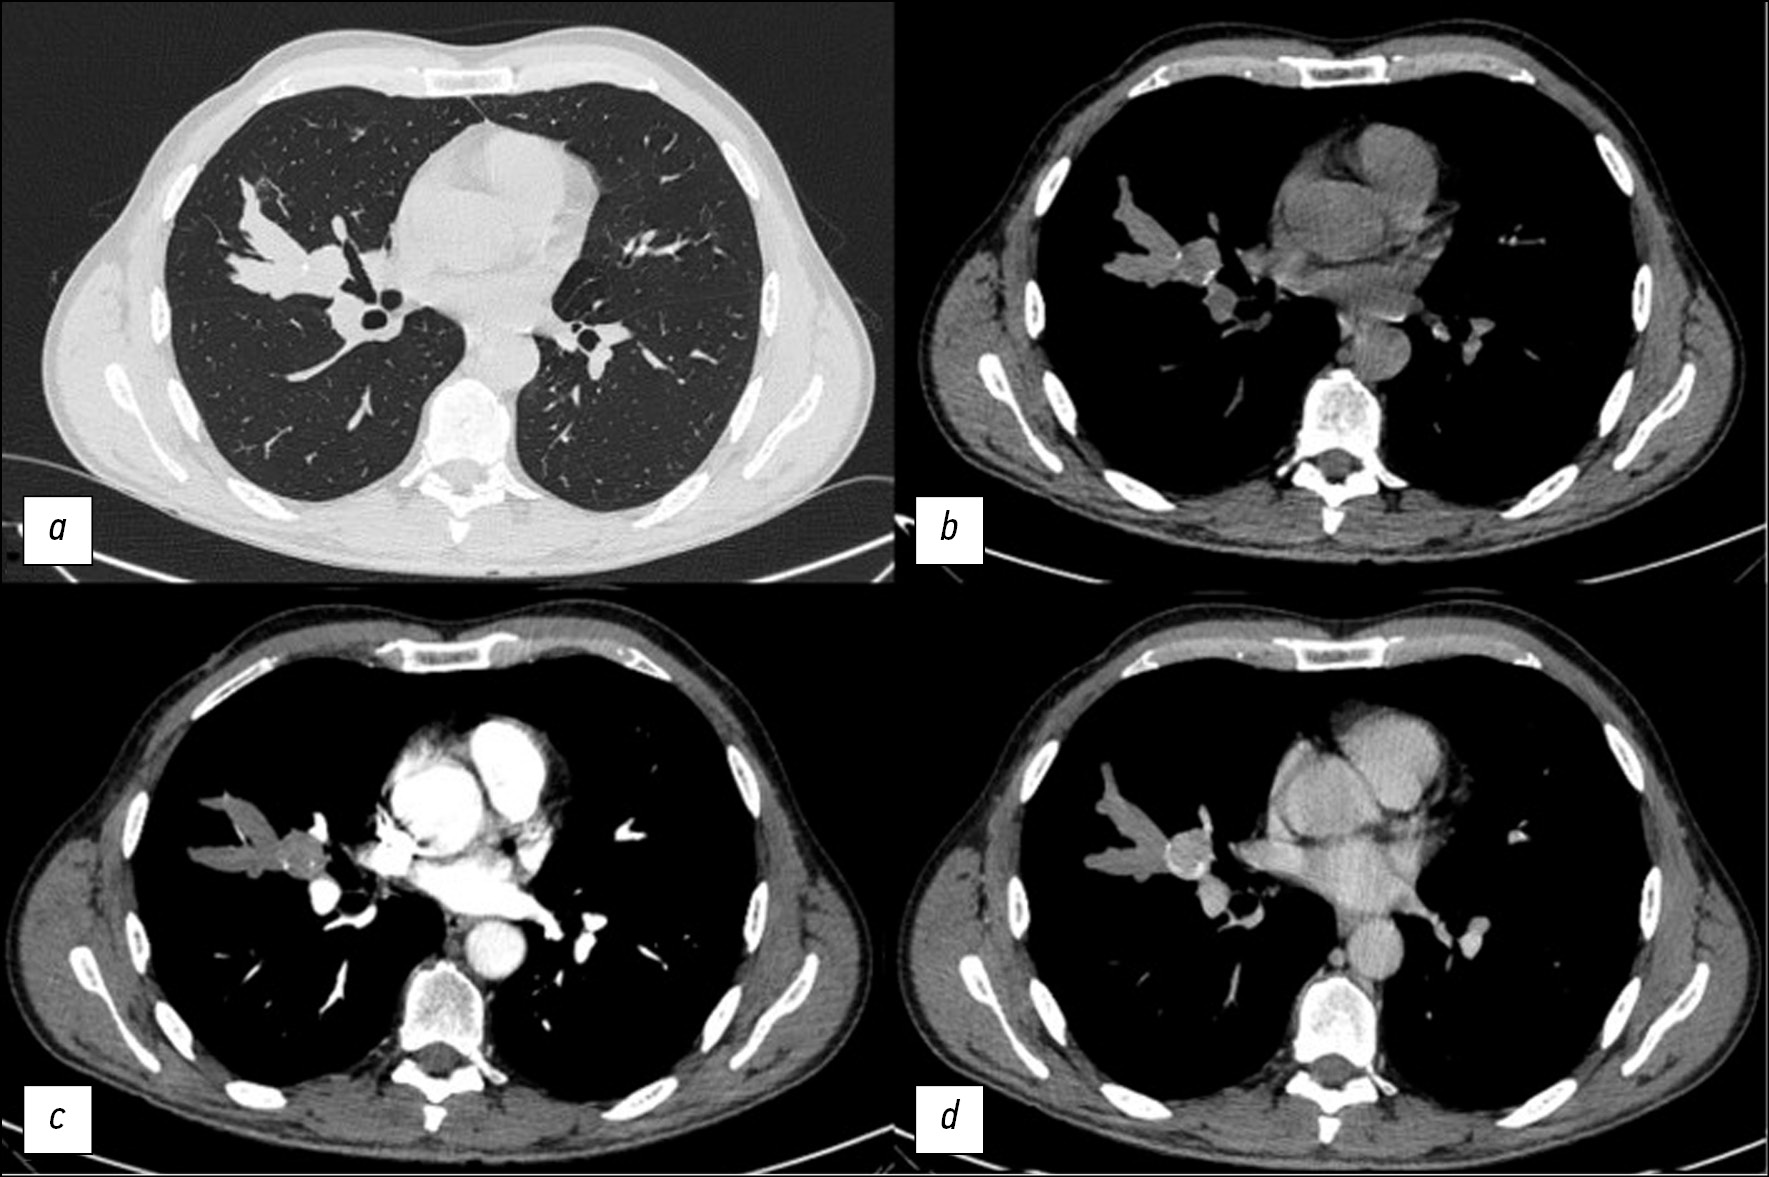

Prior to the present admission, the patient underwent a medical examination at his workplace with harmful working conditions. X-ray imaging of the chest revealed an increase in the size of the previously determined bronchocele (Fig. 1, b), as well as a new round lesion in the medial sections of the bronchocele with calcifications along the lesion contour (Fig. 1, b). To clarify the nature of the changes, the patient underwent contrast-enhanced computed tomography of the chest, which detected a single branched V-shaped structure with a clear contour in the middle lobe of the right lung, and homogeneous contents located along the subsegmental bronchi (finger in glove sign) were preserved. At the base of the bronchocele, a rounded lesion with a smooth, clear contour is noted, almost completely overlapping the bronchus B4 lumen, and single calcifications were found along the periphery with signs of contrast accumulation in the venous phase from +29 HU to +112 HU (Fig. 3).

Fig. 3. The same patient. Computed tomography of the chest cavity organs in the axial plane: a - pulmonary window, native phase (rounded formation at the base of the bronchocele); b - mediastinal window (single calcifications along the periphery education); c - mediastinal window, arterial phase; d - mediastinal window, venous phase (signs of accumulation contrast agent formation).